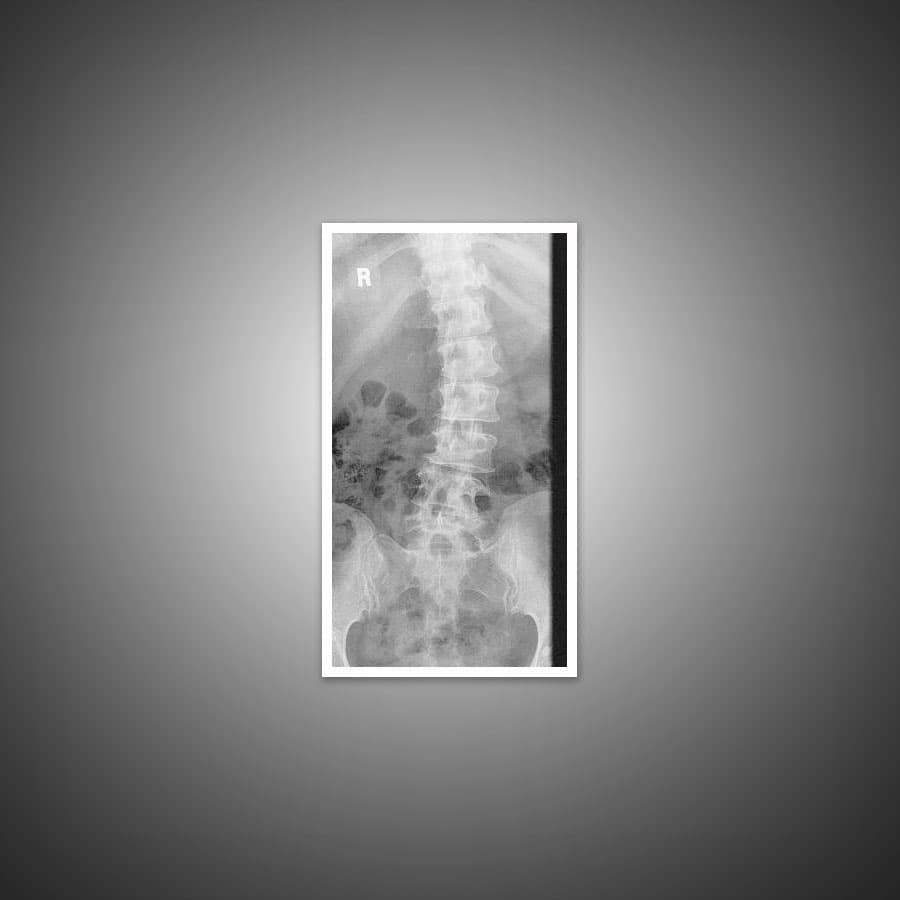

The angle of the curve can range greatly from small to large. That said, any form of curvature that measures more than 10 degrees on an X-ray is considered scoliosis. Doctors may often describe the curve using the letters “C” or “S”.

The main ways for diagnosing scoliosis are a thorough physical evaluation and a X-ray exam. Your doctor will use the X-ray to measure the degree of spinal curvature.